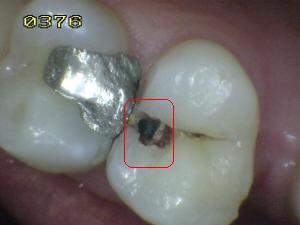

Sistema Internacional para la Detección y Evaluación de Caries (ICDAS)

¿Determine los códigos pertinentes a cada imagen?

Click en el hipervínculo: Para comparar el resultado de su diagnóstico